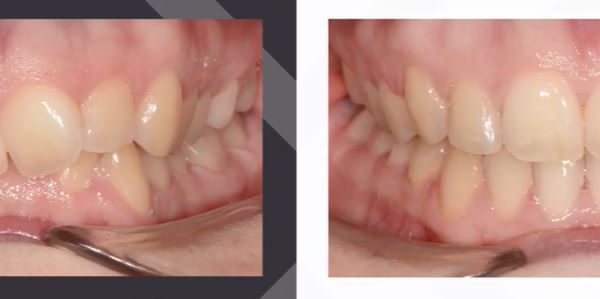

Az elmúlt évekből rengeteg szakmai referenciát tudnánk bemutatni, amelyek különböző fogszabályozási problémákat oldottak meg. Válogatva a több száz esetből, ezen az oldalon olyan képeket, információkat igyekeztünk bemutatni, amelyeknek a segítségével a jövőbeni pácienseinknek azt tudjuk üzenni: A Te fogsorod is lehet gyönyörű!

(Képeket a Pácienseink külön írásos beleegyezésével mutatjuk be!)